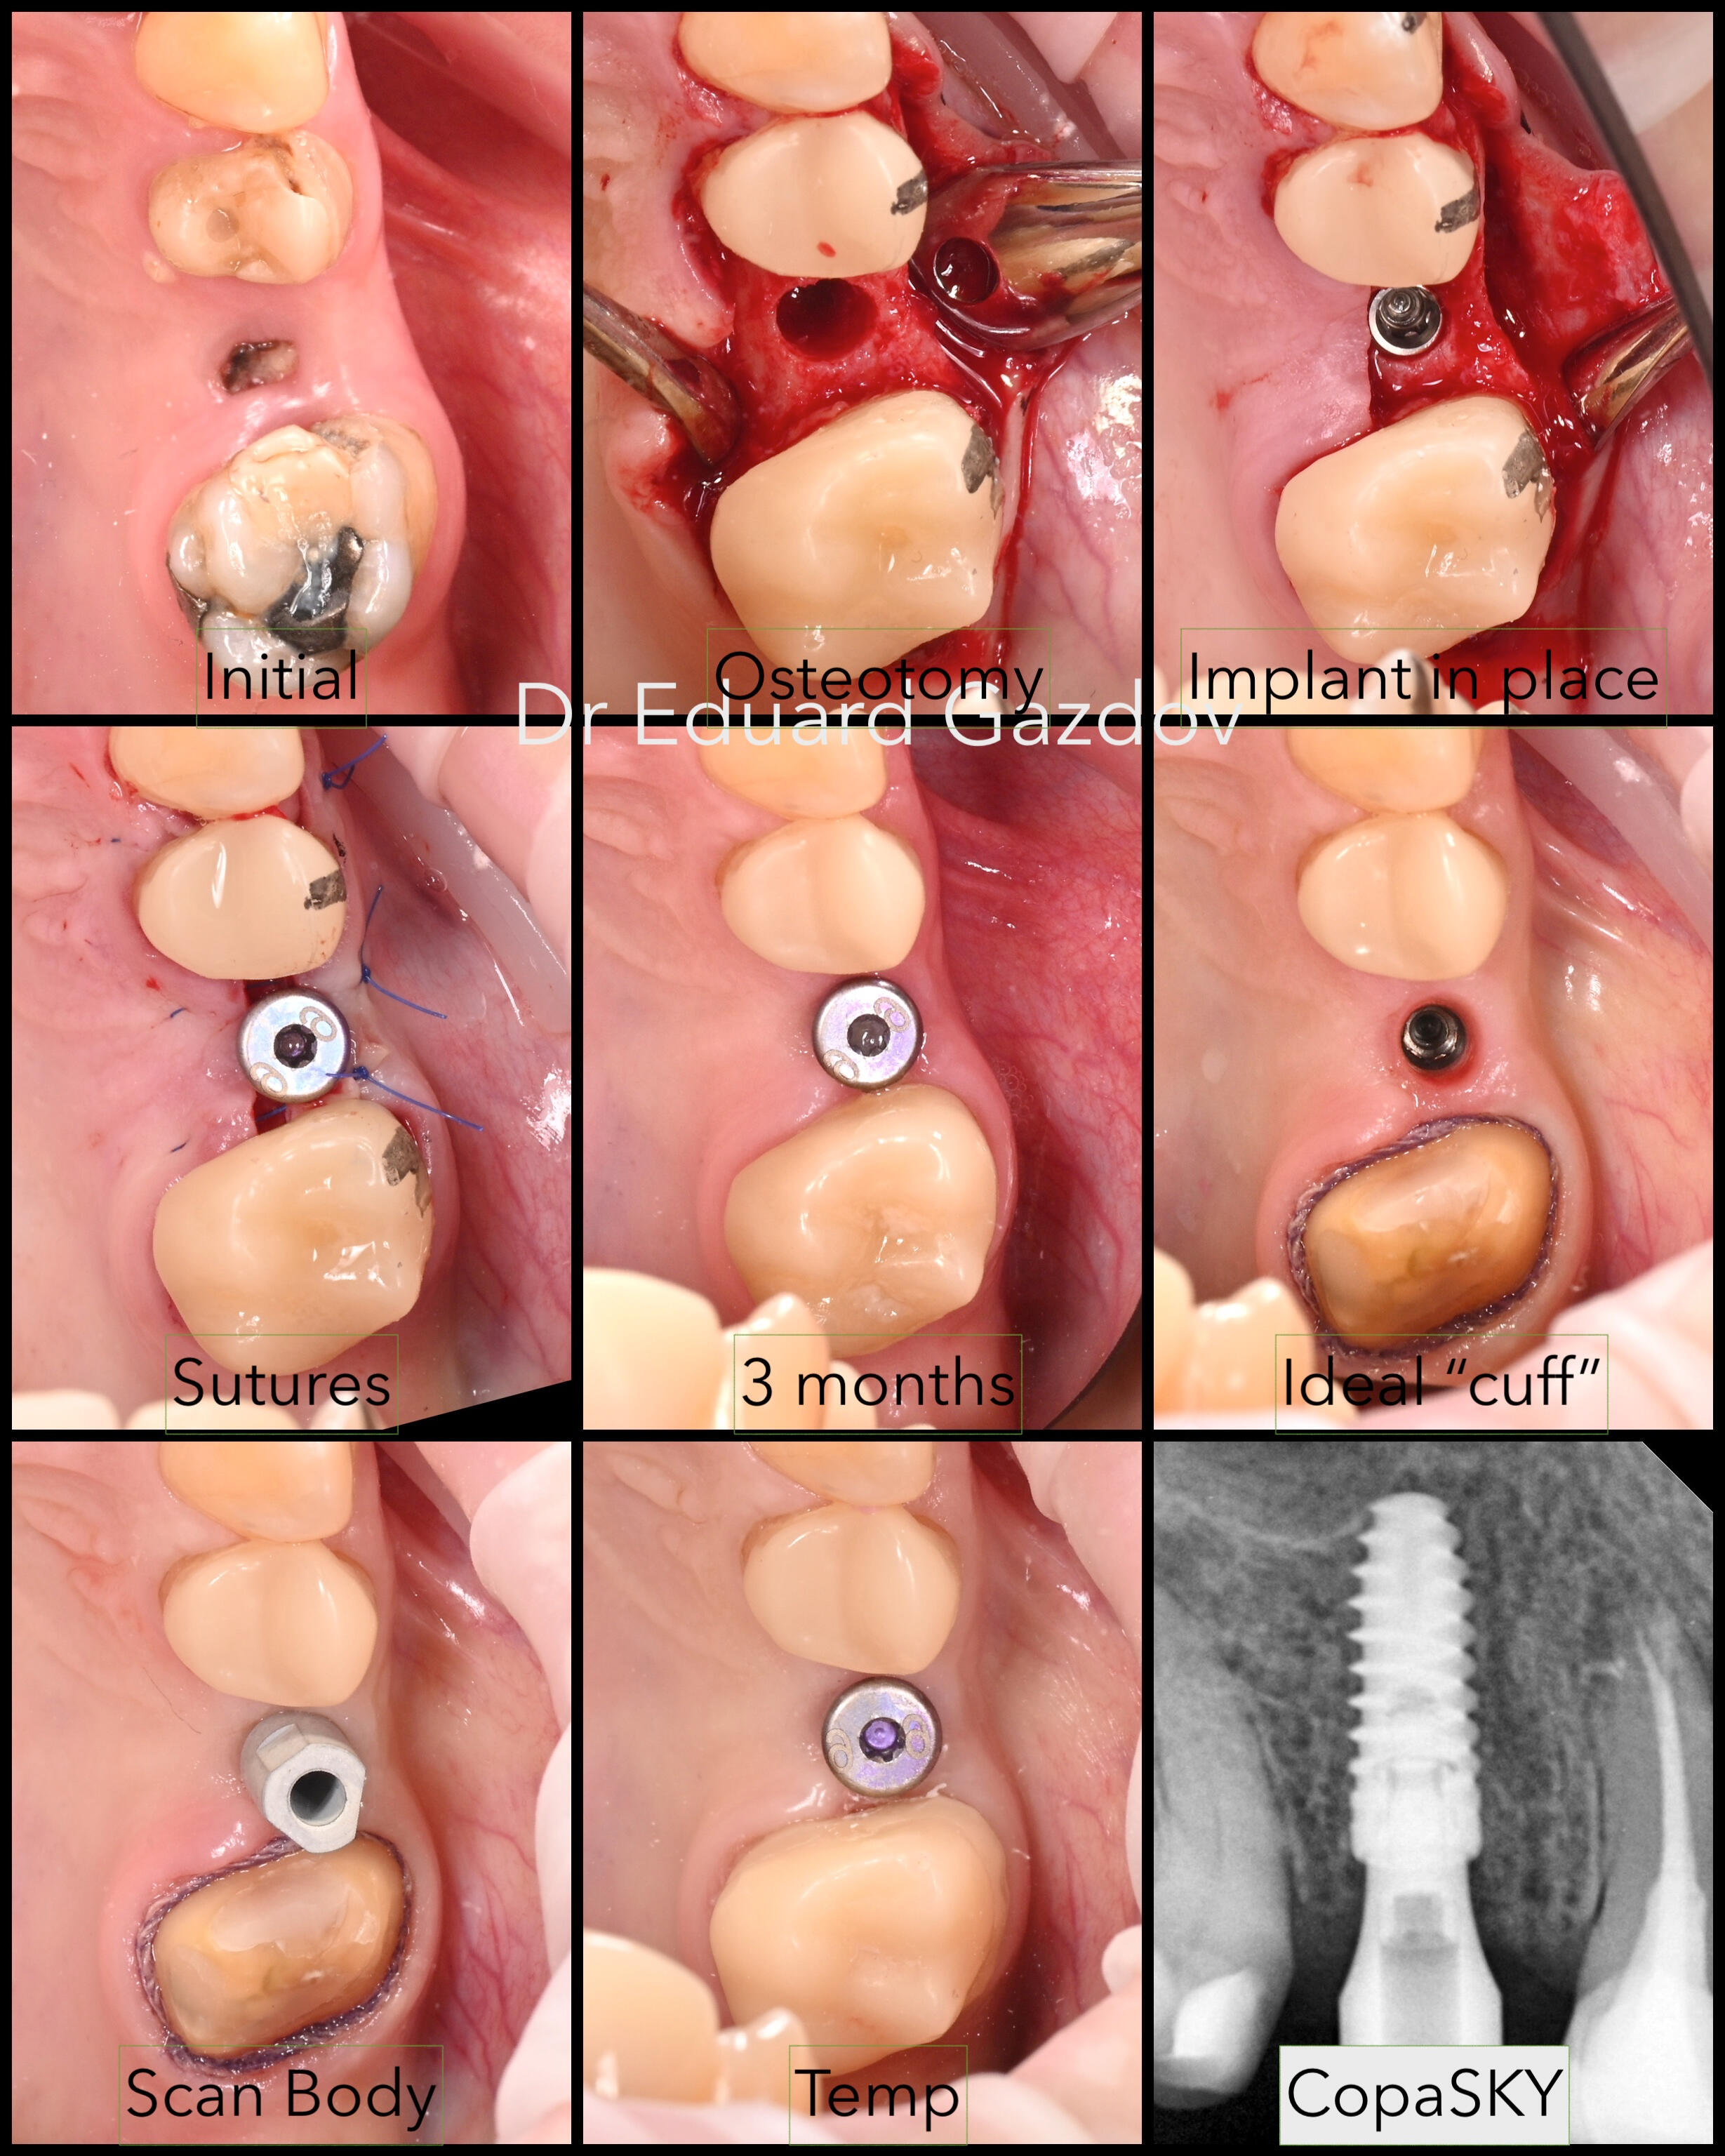

• Зъби в същия ден – кореново лечение, изграждане, дигитален дизайн и поставяне на корона в едно посещение

• Импланти с незабавно или водено поставяне – според случая и Вашите предпочитания• Фасети, корони и мостове с минимално изпиляване и естествена визия• Пълна трансформация на усмивката, планирани дигитално и изпълнени с внимание към естетиката• Хирургично вадене на зъби, включително трудни или инфектирани случаи• Директни фотополимерни възстановявания – бързо и щадящо решение при отчупвания и леки корекции• CEREC корони и инлеи, изработени и поставени на място, в рамките на часове• Прелекуване на стари канали, корони и мостовеРаботим под увеличение, използваме rubberdam, модерни дигитални технологии и най-висок клас материали.Обясняваме ясно какво правим и защо — за да се чувствате спокойни, уверени и информирани на всяка стъпка от лечението.